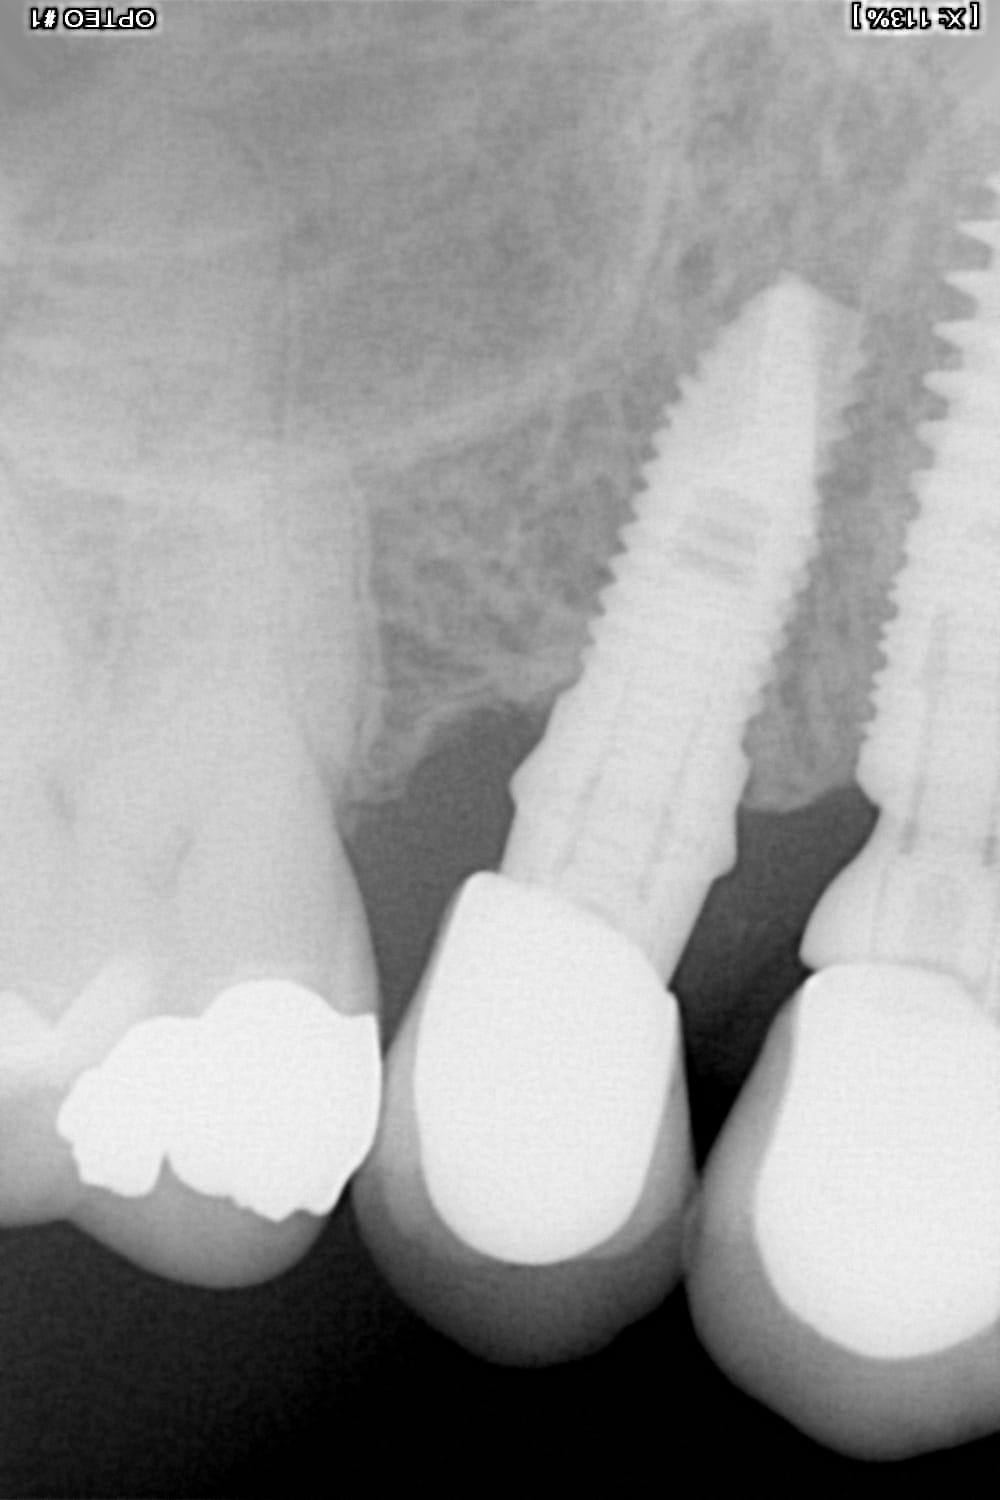

je recherche la marque d'un implant chez une patiente; voici la rétro

amha un Zimmer Spline....

https://osseosource.com/spline-twist-5-0-/p-256.html